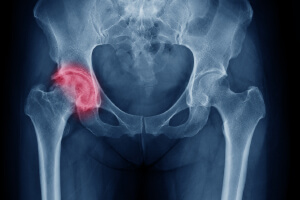

Перелом большого вертела

Чрезвертельный перелом выше большого вертела и ниже шейки бедра. Симптомы чрезвертельного перелома выражены сильнее, чем шейки бедра.

Диагноз ставят на основании рентгенографии. При внедрении отломков дополнительно используют компьютерную томографию. Консервативное лечение: гипсовая повязка сапожок или вытяжение скелета с помощью груза.

Вертельные переломы бедра возникают в зоне перехода шейки бедра в диафиз, у основания шейки бедра. Эта область окружена большим мышечным массивом. К большому и малому вертелу крепятся мощные мышцы, которые при возникновении перелома вызывают смещение отломков.